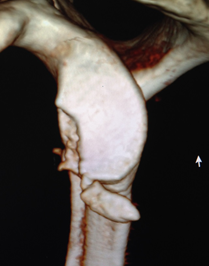

近年来,开始开展全镜下喙突移位Bristow,Latarjet手术治疗肩关节复发性脱位。目前已经可以在2个小时内完成高难度的全镜下Bristow,Latarjet手术。崔国庆教授受到中国古建筑学中“榫卯”结构的启发,将之引入经典的Bristow手术中,在国际上首创关节镜下改良“嵌入式”喙突移位(Bristow)手术,并将其命名为CUIstow手术(Chinese Unique Inlay Bristow),通过增加骨接触愈合面积,显著增加了移植喙突骨块的稳定性并且极大提高了术后的骨愈合率。截至目前为止,该手术技术在课题组所在单位已经成功实施400余例,3年中期随访结果显示,术后骨愈合率达到了96.4%,并发症的发生率仅为3.6%,术后重返运动比率达到了98%,取得了非常良好的临床效果以及患者满意度。相关成果发表在国际运动医学领域权威期刊American Journal of Sports Medicine,AJSM和国际骨与关节领域权威期刊Journal of Bone & Joint Surgery,JBJS。

在国际上首创关节镜下改良“嵌入式”喙突移位(Bristow)手术,并将其命名为CUIstow手术(Chinese Unique Inlay Bristow)